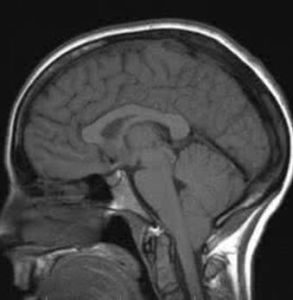

小腦扁桃體鄰近延髓和枕骨大孔的兩側,當顱內壓增高時,小腦扁桃體有可能受擠而嵌入枕骨大孔,造成小腦扁桃體疝(枕骨大孔疝),壓迫延髓,危及生命。

小腦扁桃體:小腦扁桃體位於小腦半球下方一對明顯的隆起,叫小腦扁桃體。此扁桃體正位於枕骨大孔上方,腦壓增高或附近發生腫瘤時可將其擠壓入枕骨大孔外,即為枕骨...

小腦扁桃體疝(枕骨大孔疝)

由於顱內高壓或後顱窩占位病變將小腦和延髓推向枕骨大孔並向下移位。 疝入枕骨大孔的小腦扁桃體和延髓形成圓錐形,腹側出現枕骨大孔壓跡。

當顱內某一分腔有占位病變,該分腔的壓力比鄰近分腔的壓力要高,於是壓力高的部位腦組織向壓力低的部分擠壓、移位,即是腦疝。枕骨大孔疝又稱小腦扁桃體疝,大多發...